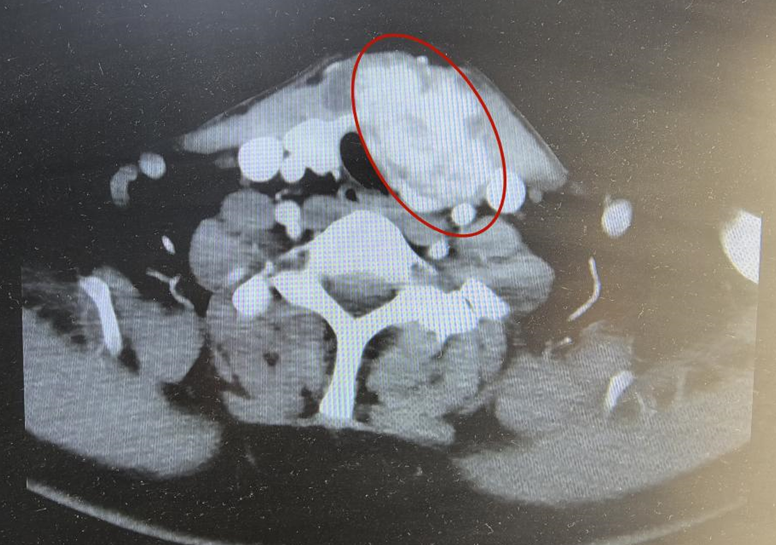

CT檢查發現,他頸部左側有一個巨大甲狀腺腫瘤,直徑達到了6cm,幾乎有鴨蛋大小,而且腫瘤侵犯了頸部肌肉,氣管,食管和頸部大血管。

于是抱著一絲希望,他來到北大深圳醫院乳腺甲狀腺外科。接診的李朋副主任醫師發現鴨蛋大的腫瘤把氣管壓迫成了一個窄縫,侵犯了頸部肌肉、氣管、食管和頸內靜脈,同時可見頸部淋巴結多發轉移,初步診斷為“局部晚期甲狀腺癌”。

幸運的是,馬強在接受3個月多納非尼治療后,奇跡逐漸顯現,腫瘤負荷的血液指標下降明顯。復查頸部CT顯示,腫瘤從一個“鴨蛋”縮小成一個“雞蛋”,最長徑較前縮小1.5cm,短徑較前縮小0.5cm,氣管壓迫減輕,頸部多發淋巴結轉移也較前縮小。

“腫瘤縮小后,氣管和腫瘤之間就有間隙,手術完整切除腫瘤的成功概率就有了。”李朋說。尤其是CT顯示腫瘤內部密度和血供明顯減低,這說明腫瘤活性在下降,為后續手術創造了條件。